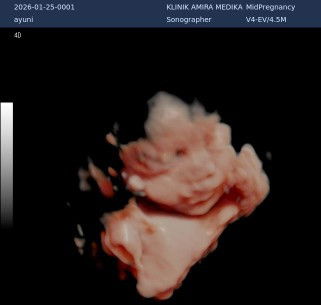

ini mnrt moms nrmal kan ya bibirnya kt dktrnya nrmal tp aku ovt stlh usg mnm vit ditm1 aja soalnya😢

anak ku kmrn di USG jga nampak ny gtu mba

keliatan Gemoy 😊 jadi mulut nya manyun

sama bun, ga pp insyaallah semua normal.

iya bun bener, kita sama. tapi aku mulai mempositif thinking kan pikiranku selagi dokter bilang engga pp🙏